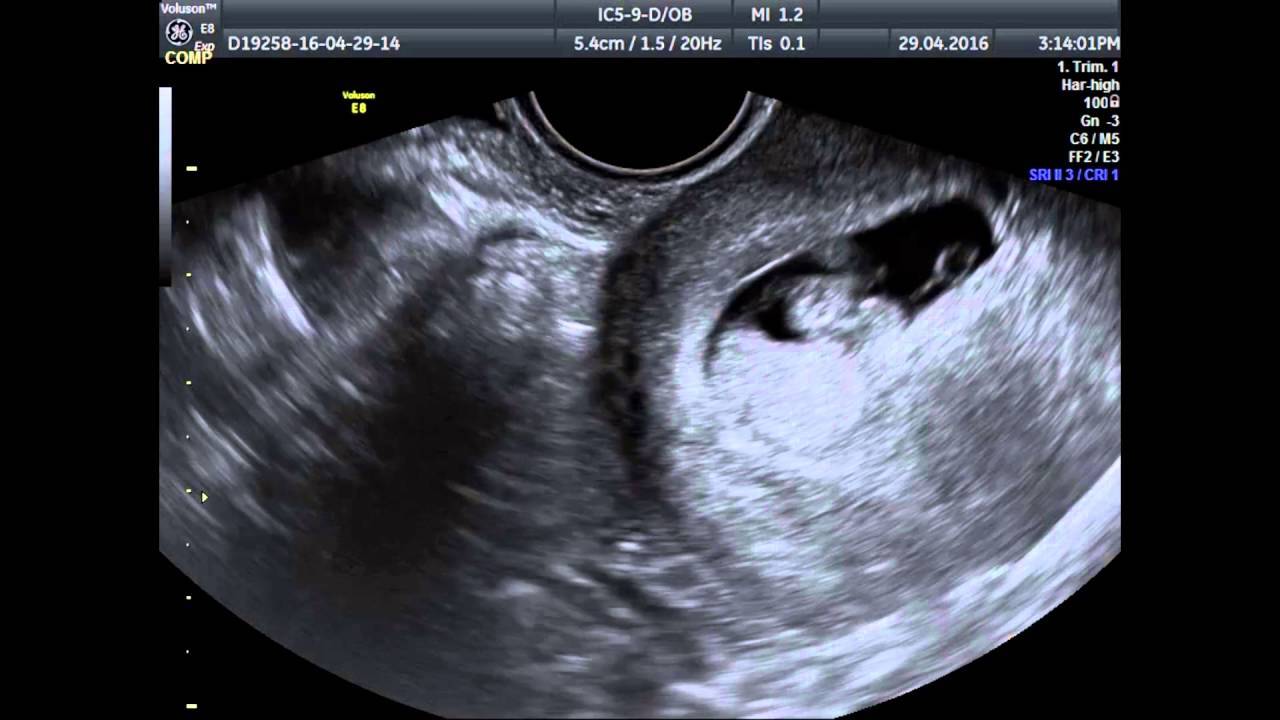

Среднестатистически определено, что визуализация эмбриона осуществима в 7 недель от даты зачатия, при активном проходящем росте уровня ХГЧ в крови. Однако, если даже на таком сроке специалисты не увидели эмбрион в плодном яйце, впадать в панику нужно только если остановился рост уровня ХГЧ или же он пошел на спад. Такая картина свидетельствует о том, что беременность замершая. Однако, удостовериться в этом лишний раз не помешает, поэтому стоит перепроверить все у другого врача или же сделать УЗИ трансвагинально.

Ошибка в определении срока гестации, погрешности работы оборудования и сонолога

Если во время обследования плод не визуализируется, причина чаще всего кроется в неправильном определении срока беременности. Когда УЗИ делается на 3 или 4 неделе гестации, ультразвуковой аппарат не в состоянии зафиксировать наличие эмбриона в маточной полости. До 5-недельного срока размеры плодного яйца не превышают 2 мм, что делает невозможным его визуализацию.

Зародыш зачастую не лоцируется в матке из-за особенностей УЗ-сканера. Чтобы «увидеть» эмбрион, аппарат должен обладать определенной чувствительностью. Кроме того, его неисправность также может исказить изображение на мониторе, в результате чего диагност не сможет подтвердить факт беременности.

Когда виден эмбрион?

Многих интересует вопрос, на какой же неделе видно эмбрион на такой процедуре как УЗИ. Нужно сказать, что плодное яйцо можно увидеть на обследовании уже примерно с 2,5 недель беременности. На УЗИ оно выглядит темным округлым образованием, которое окружено тонкой оболочкой и имеет в диаметре до 5 мм. Сам эмбрион еще слишком мал, чтобы его рассмотреть.

5 недель. Хорошо виден плодный мешок, а также отек эндометрия

На этом сроке УЗИ используется для того, чтобы подтвердить саму беременность. Через пару недель плодное яйцо становится больше и гораздо заметнее. К четырем неделям беременности оно равняется в диаметре примерно 2 см, увеличивается матка. На каком же сроке видно сам эмбрион на экране аппарата УЗИ? Разглядеть его можно только с пятой недели беременности: видно будет продолговатый объект, крепящийся будущей пуповиной к стенке плодного яйца.